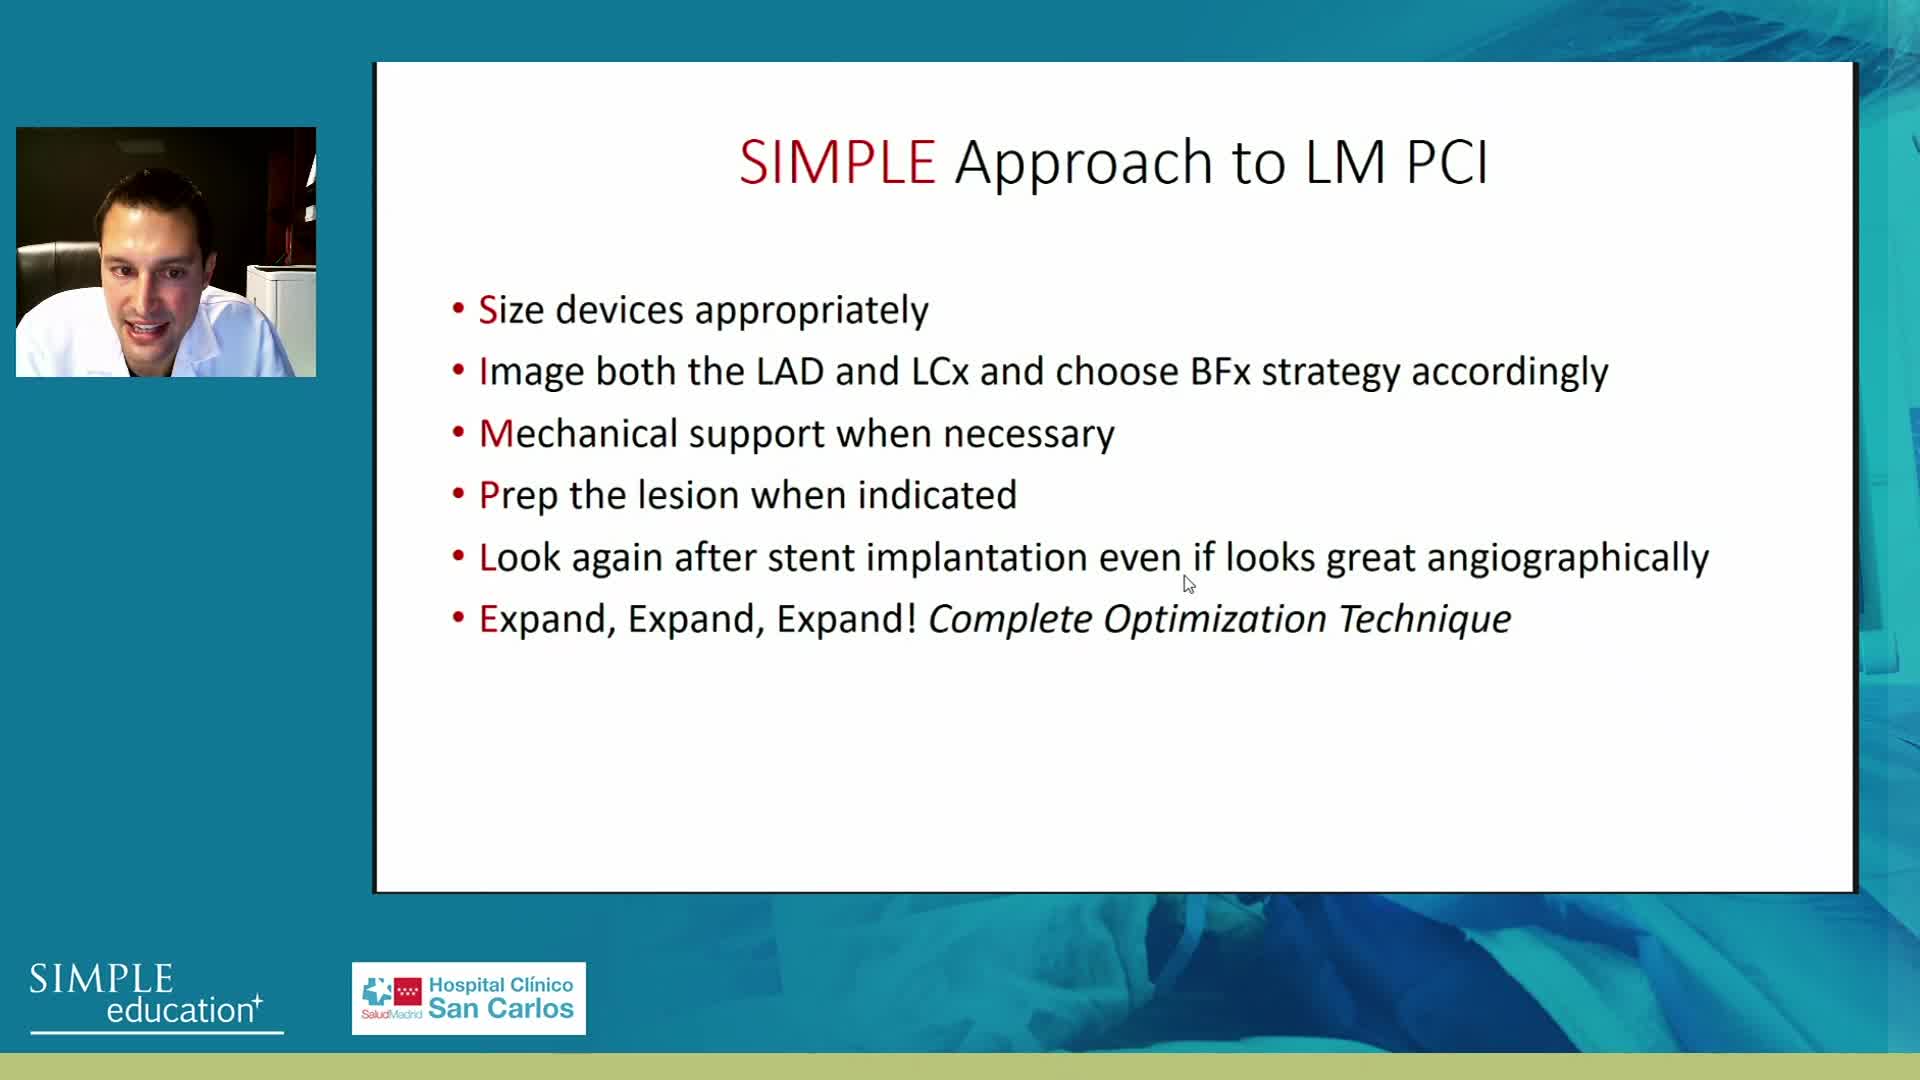

Advanced PCI Course Content

Best practices and personalised medicine in complex PCI - Prof Javier Escaned